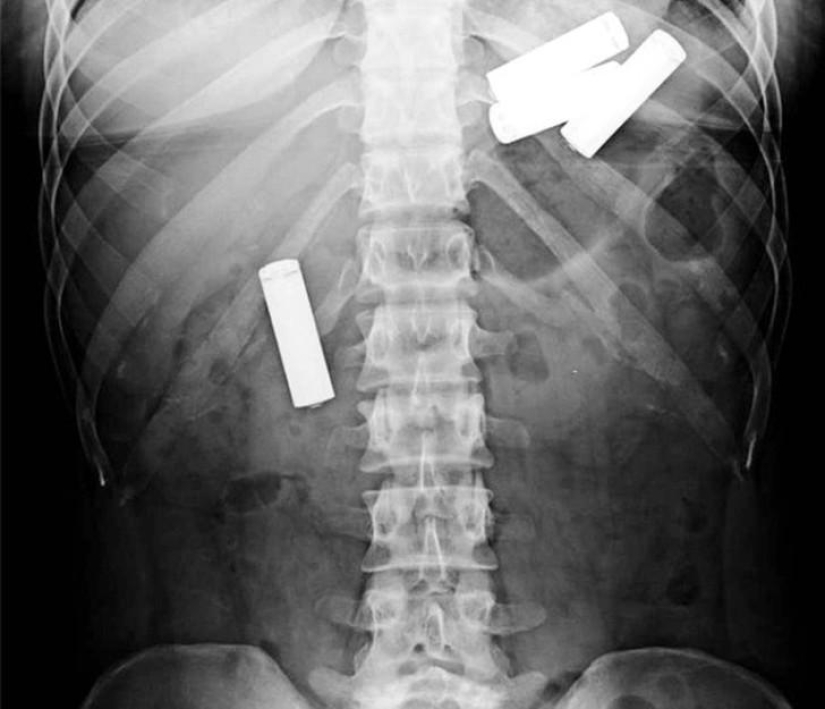

Pinzas.